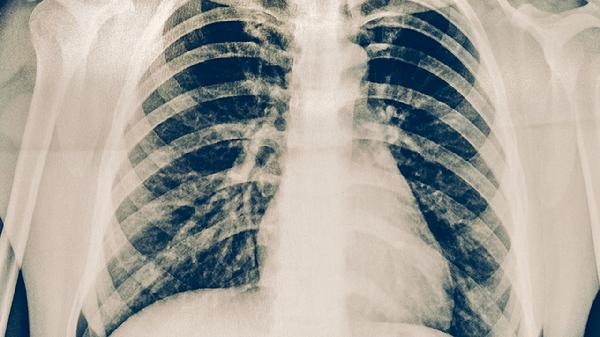

医务人员、矿工等职业人群因频繁接触粉尘或患者,呼吸道黏膜防御功能受损,易通过气溶胶感染。这类患者常出现乏力、食欲减退等全身症状。防护措施包括佩戴N95口罩,定期进行胸部X线筛查,必要时预防性使用异烟肼维生素B6片。